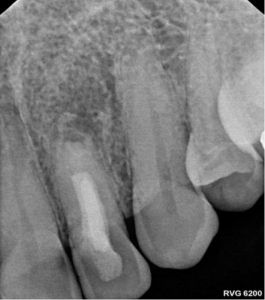

After 11 months, we’re thrilled to report significant improvements:

- Resolution of the apical lesion

- Acceptable healing around the root tip

- No tenderness or discomfort

While the outcome isn’t perfect, it’s a remarkable success given the tooth’s history and condition.